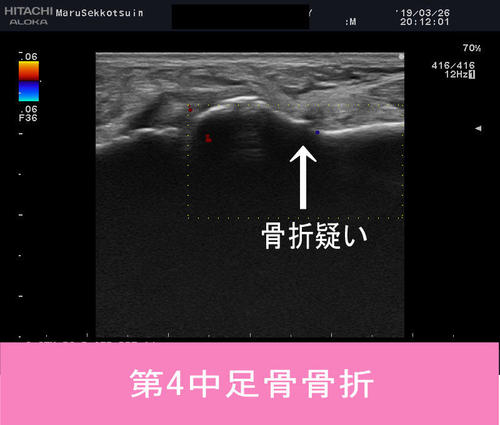

確認の為、エコー検査

やっぱり骨折、疑わしい陰影、、、

しかし今回は「第4中足骨骨折」の疑い。